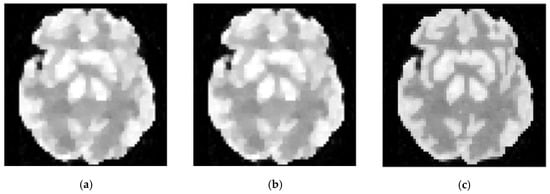

Figure 8.

The 15th frame of 111 111 sized Zubal head phantom reconstructed by different algorithms. (a) ground truth, (b) ML-EM (18.19 dB), (c) PWLS (18.35 dB), (d)TV-AL (19.22 dB), (e) PLH-IO (19.17 dB), (f) ST-TV (19.45 dB), (g) Ours (19.73 dB).

Meanwhile, our method also shows its universality in recovering sequences under different sizes and TACs. In this experiment, 111 111 sized Zubal head phantom data were tested in an 18F-FDG environment. In Figure 8, the 15th frame is randomly selected out of 24 frames. In addition, real patient data are tested. In Figure 9, the second sequence is shown, and the photon counts are around 2.2 105. Obviously, our proposed method yields clearer boundaries and more conspicuous contrast between ROIs and the background.